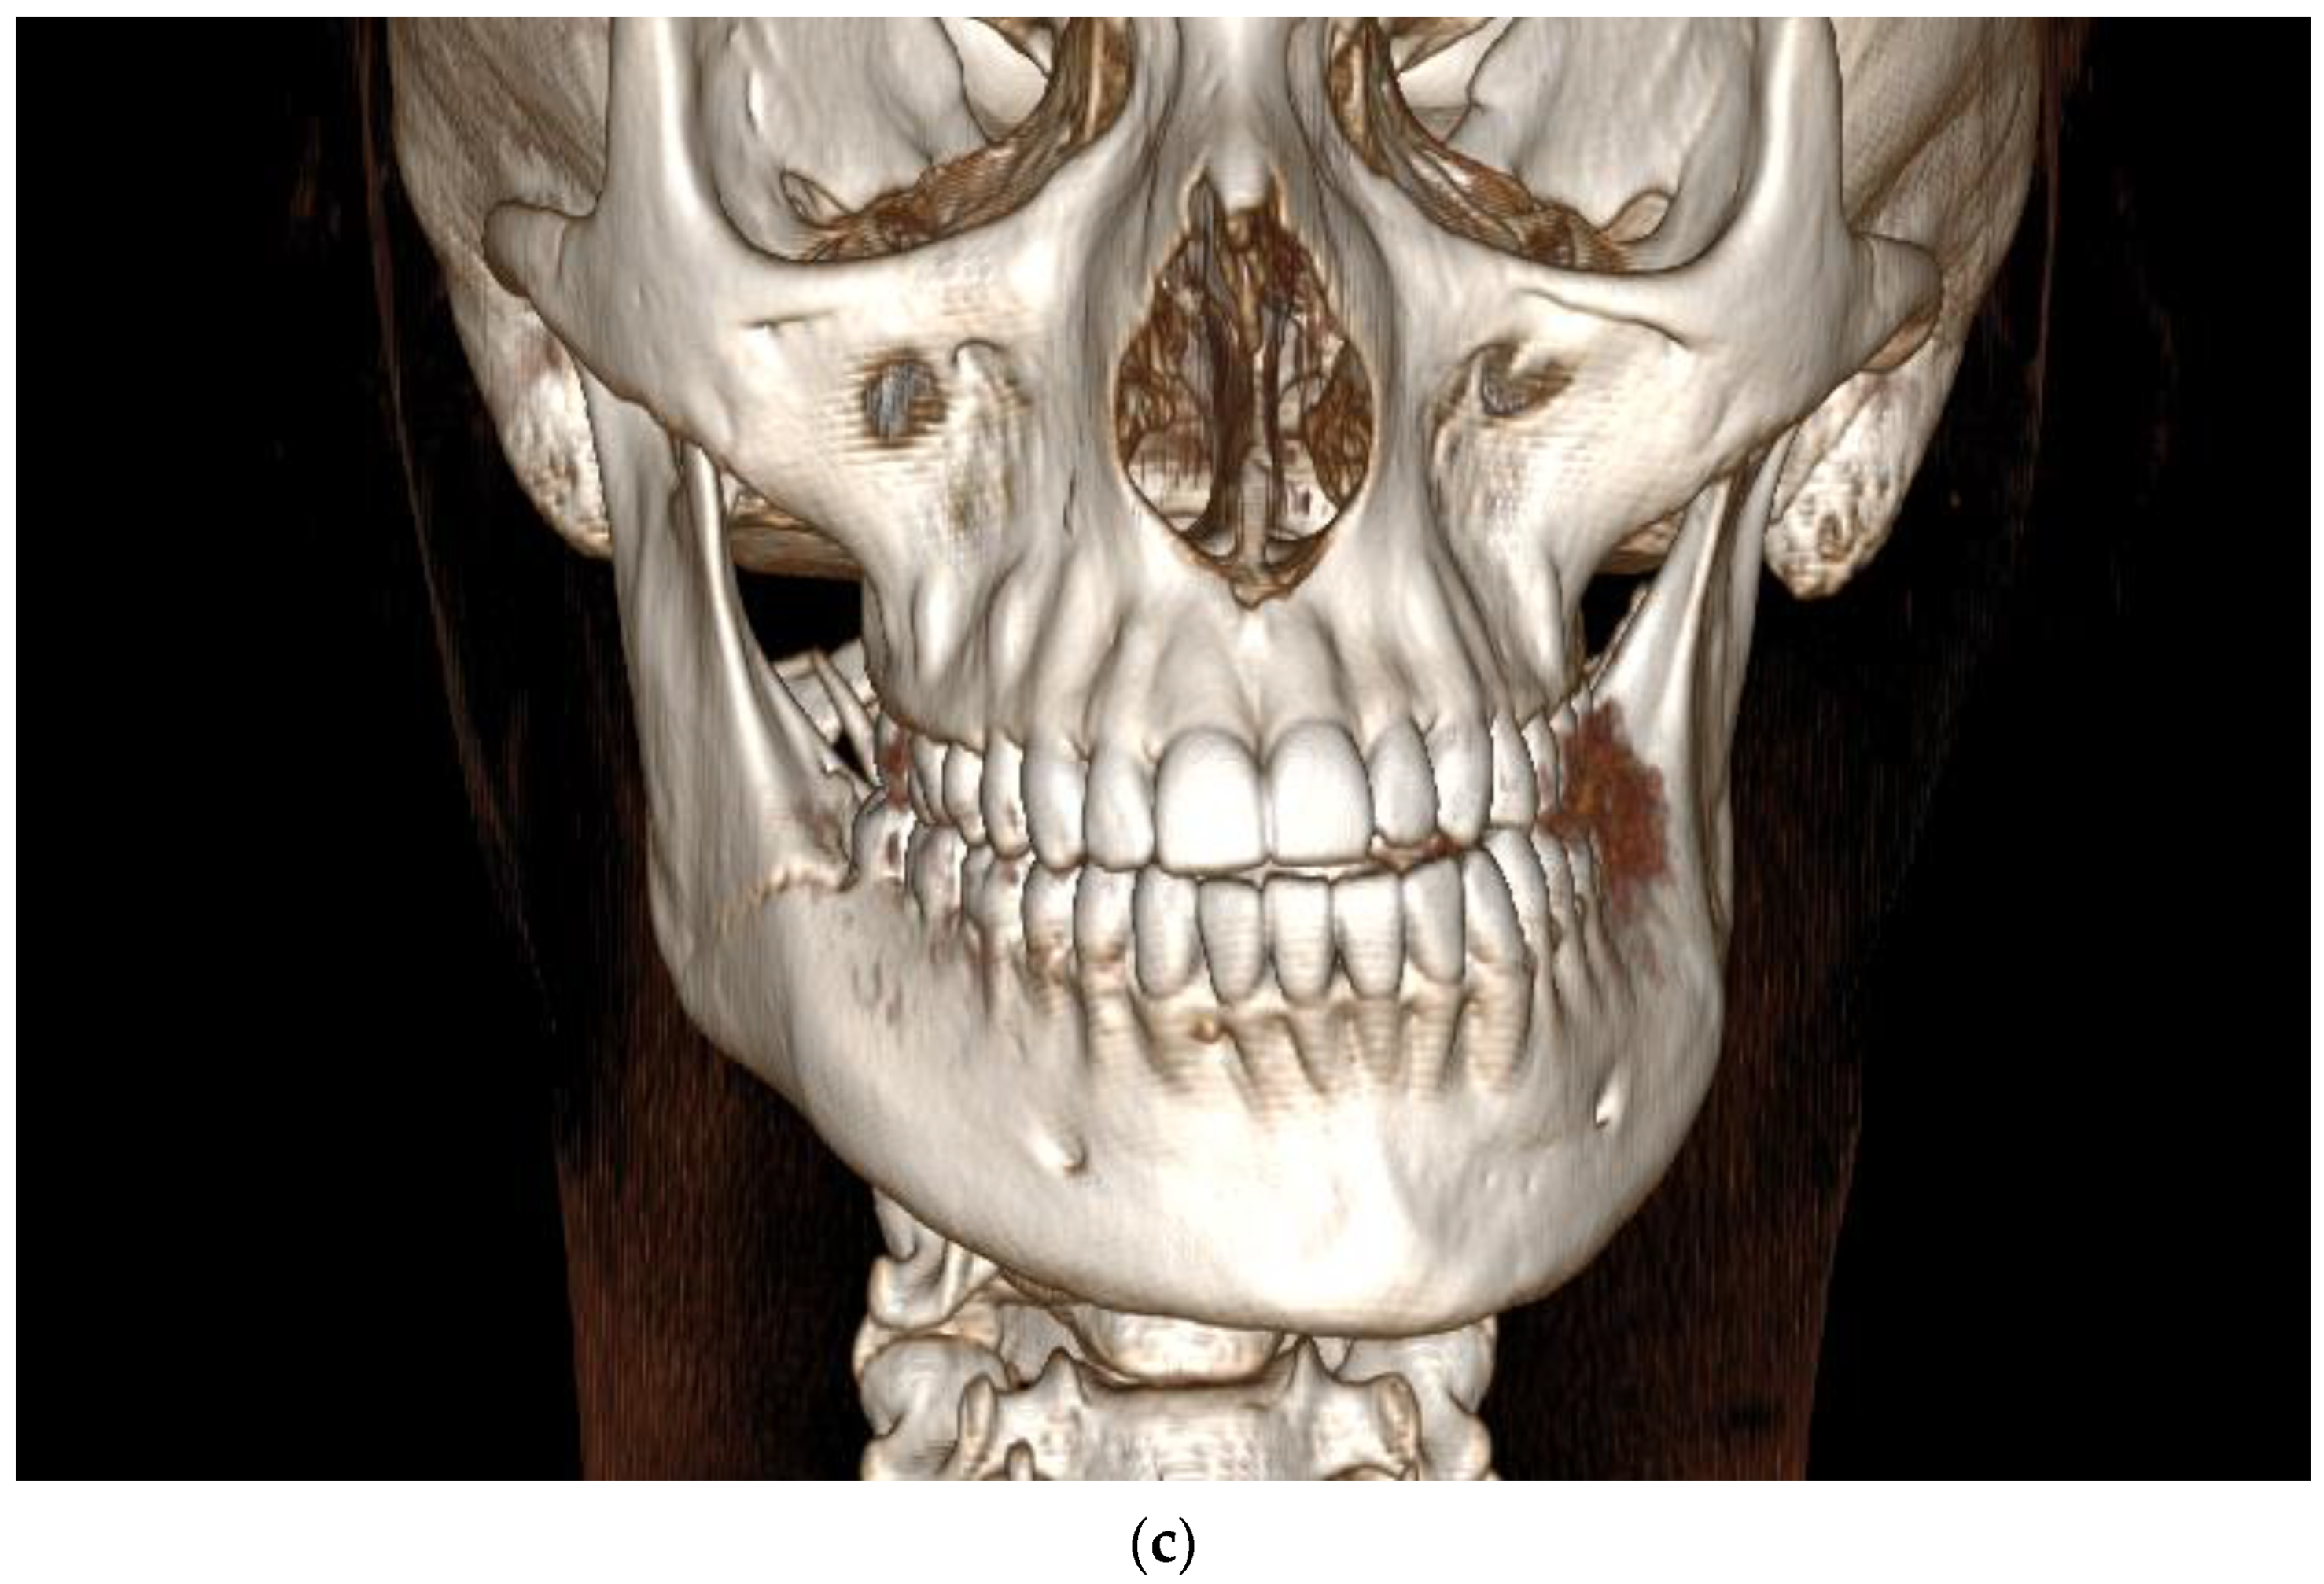

3.1. Case 1

3.2. Case 2

3.3. Case 3